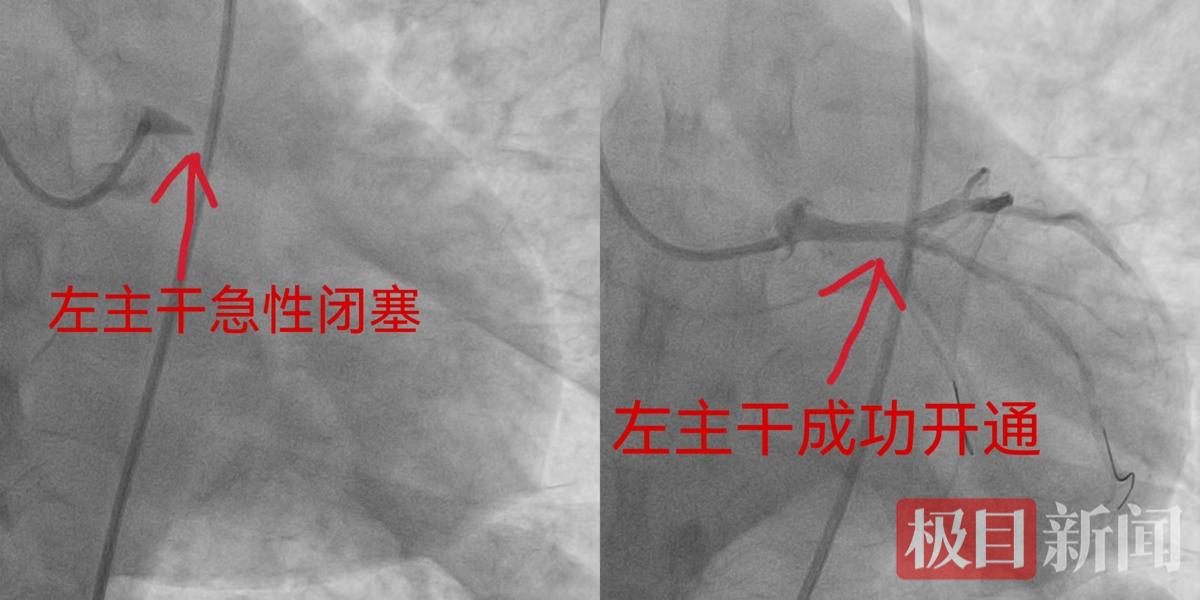

该院胸痛中心绿色通道随即启动,导管室同步备勤,医护团队争分夺秒,为赵先生开展急诊介入治疗,每一秒都在与死神赛跑。面对这一高危复杂病变,在“黄金救治窗口期”内,武汉市普仁医院心血管内科任浩进主任和介入团队凭借丰富的临床经验与娴熟的介入技术,迅速完成冠脉造影,明确诊断为左主干完全闭塞。冠状动脉左主干是心脏供血的“总闸门”,一旦急性闭塞,将导致约80%的心肌血供中断,死亡率高达90%以上,长期以来被视为经皮冠状动脉介入治疗(PCI)的“禁区”。

术中,团队精准操作,顺利将导丝通过闭塞段,成功植入支架,恢复了心脏关键血流,成功打通“生命主干”。为保障患者术后安全,赵先生术后被转入心血管内科重症监护病房(CCU),接受循环支持、抗凝、抗心律失常及多器官功能维护等精细化综合管理,为后续康复筑牢基础。